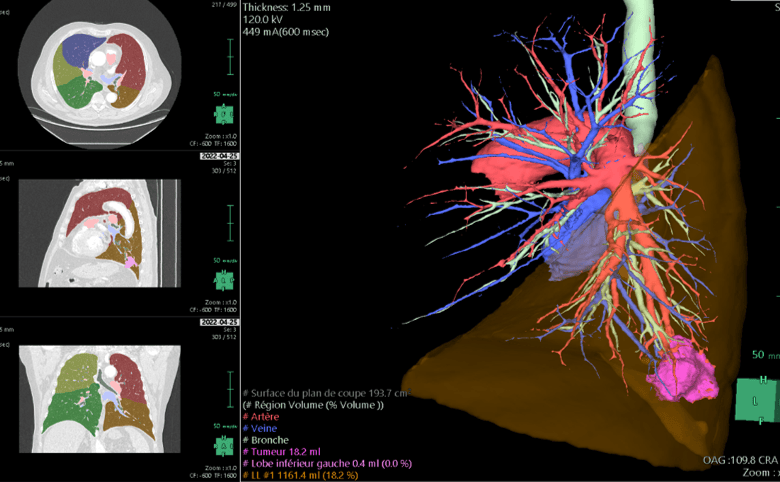

Reconstructions 3D

De quoi s’agit-il ?

Nous reconstruisons l’anatomie du patient en 3 dimensions grâce à un scanner thoracique (en utilisant le logiciel Synapse 3D) avant l’opération afin de la préparer car chaque patient est unique et chaque anatomie est différente.

A quoi ça sert ?

Les reconstructions 3D permettent au chirurgien de :

- diminuer la durée de l’intervention chirurgicale grâce à un gain de temps de dissection

- planifier le déroulé de l’intervention chirurgicale, c’est-à-dire , prévoir les étapes de dissection de l’organe

- réaliser des interventions plus complexes qu’auparavant grâce à une meilleure précision de la connaissance de l’anatomie du patient qui est soigné

- diminuer le risque d’erreur anatomique pendant l’opération quand les patients ont une anatomie inhabituelle

- diminuer le risque d’accident hémorragique lors de l’intervention

- améliorer les marges de résection de sécurité d’une tumeur en augmentant ainsi la qualité oncologique du geste